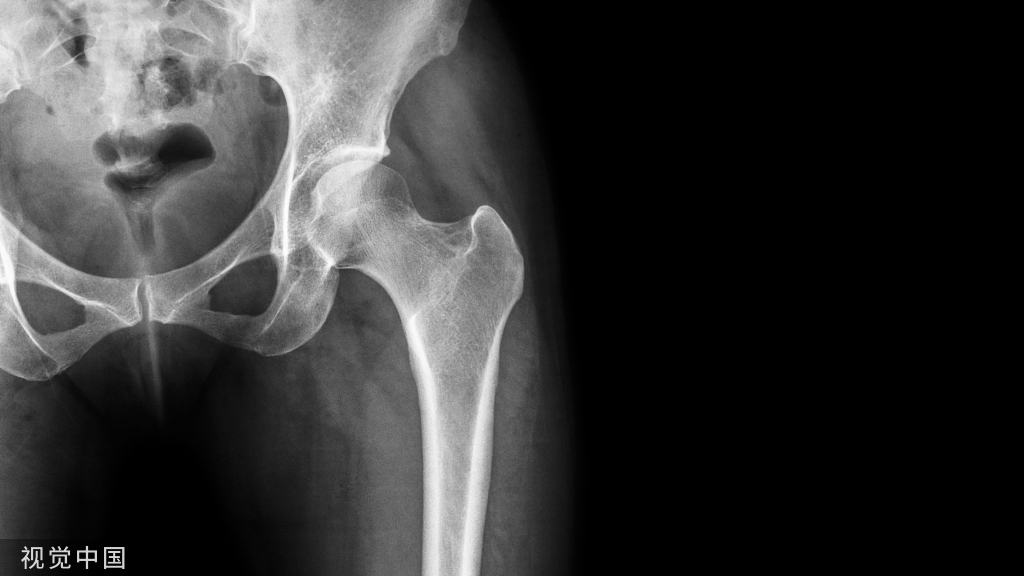

患者,男,56岁,脑外伤及下肢开放伤,急诊手术未使用双氧水,生理盐水冲洗伤口,外固定架固定,伤口游离植皮闭合。骨折及伤口获良好愈合